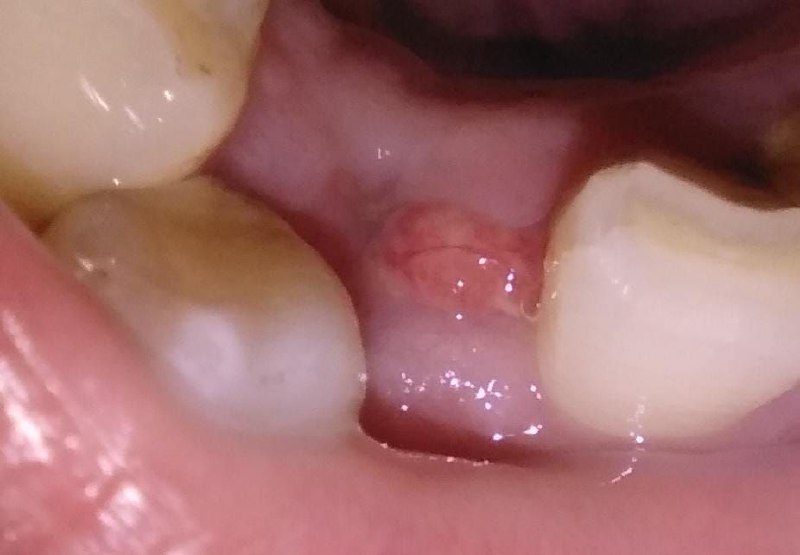

Me sacaron una muela y me salió una bolita de carne

En muy pocas ocasiones luego de una extracción de una muela del juicio la pasar días, puede aparecer un pequeño bulto en la encía, puede ocurrir que se formen luego de la extracción quistecillos residuales o también formarse una pequeña infección.

En estos casos las soluciones de toma de una radiografía para valorar el tratamiento adecuado que podrá ser la toma de un antibiótico, o si es necesario una pequeña incisión para remover lo que causa la lesión.

Recomendamos siempre acudir a consulta para que su dentista sea quien valore el protocolo odontológico a seguir.